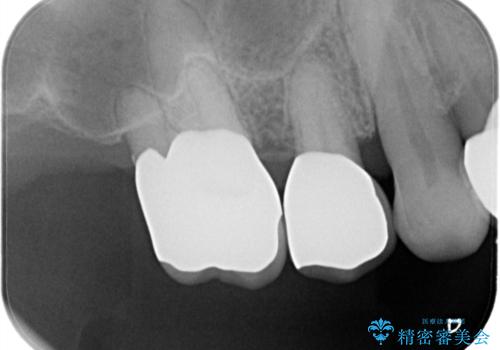

歯周病の進行した歯の抜歯。オールセラミッククラウン

- 以前に他院にて治療した歯が痛いことを主訴に来院されました。

最後方臼歯は根尖部まで歯周病が進行しており、抜歯を行なったのち、残存歯は歯周外科を行なったのちオールセラミッククラウンにて修復治療を行なっています。